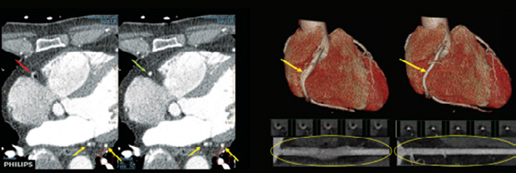

Klaudyna Stefańska, Weronika KubarekPhilips Sztuczna inteligencja AI (Artificial Intelligence) staje się nieodłącznym elementem w nowoczesnych systemach tomografii komputerowej. Początkowo sztuczna inteligencja była postrzegana przez lekarzy i techników jako konkurencja. Jednak wraz z upływem czasu korzyści płynące z zastosowania AI przeważają nad tymi obawami i obecnie ciężko wyobrazić sobie system, który nie wykorzystuje jej do pracy.…